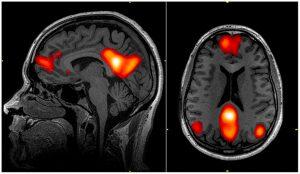

Kun koemme kipua, aivotoiminta on luonnollisesti kohonnutta niillä aivoalueilla, joissa käsitellään akuuttia kipua tai alueilla, jotka liittyvät krooniseen kipuun. Näistä alueista puhutaan kollektiivisesti ”kipumatriisista” [1]. Aivoihin kulkeutuvien nousevien nosiseptiivisten ratojen kulku voidaan teoreettisesti jakaa kahteen polkuun – lateraaliseen ja mediaaliseen rataan. Lateraalinen polku synapsoituu hyvin suoraviivaisesti talamuksen kautta somatosensoriselle aivokuorelle (S1, S2), ja näin tulemme tietoiseksi kivusta ja sen sijainnista. Mediaalinen rata puolestaan onkin monimutkaisempi, nimittäin se kytkeytyy useisiin aivoalueisiin, jotka liittyvät kognitiivisiin, emotionaalisiin ja hormonaalisiin toimintoihin. Mainittakoot tärkeimpinä alueina anteriorinen cingulate korteksi (ACC), Insula, amygdala, hypotalamus ja prefrontaalinen korteksi (PFC).

Mainittavana asiana pitäisin myös sitä, että jopa 85% nousevista C-säikeistä (nosiseptiota kuljettavat säikeet) synapsoituvat retikulaariseen muodostelmaan (reticular formation), jonka aktiivisuus huolehtii muun muassa edellä mainittujen kognitiivisten ja emotionaalisten keskuksien ”herätevasteesta”. Joten ei ihme, että pitkäaikainen kipu voi aiheuttaa voimakkaita emotionaalisia reaktioita, kuten pelkoa, ahdistusta, hypervigilanssia ja katastrofisointia. Tämä puolestaan voi stimuloida entisestään nosiseptiivisia hermoratoja, jota voidaan kutsua myös kognitiivisemotionaaliseksi sensitisaatioksi [2].

Aivojen oletushermoverkko (Default Mode Network) on yksi laajoista aivoverkoista, joka liittyy useisiin kognitiivisiin toimintoihin, kuten sisäisten tunnetilojen havainnointiin ja tarkasteluun, spontaaniin ”ajatusten juoksuun”, keskittymiseen, muistiin ja luovuuteen. Tämä hermoverkko tyypillisesti aktivoituu, kun aivot ovat lepotilassa, eli siis kun pysähdymme ja emme tee mitään, esimerkiksi kun makaamme sohvalla ja annamme ajatuksen virrata. Kun keskitymme suorittamaan jotain spesifiä tehtävää, oletushermoverkon tulisi sammua ja puolestaan suorituskeskeisen hermoverkoston tulisi ottaa tilanne haltuun aivoissa. Eli normaalisti aivoissa toimii aina yksi verkkotoiminta kerrallaan. Aivokuvantamistutkimuksissa on havaittu kroonisesta kivusta, stressistä ja aivotärähdyksen jälkeisestä oireyhtymästä kärsivillä oletushermoverkon muuttunutta toimintaa sekä vaikeuksia sammuttaa tätä, kun suorituskeskeisen verkkotoiminta aktivoituu [3-6]. Kun kaksi verkkotoimintaa on aktiivisena yhtä aikaa, ihmisen on vaikea keskittyä ja aivot kuluttavat kaksinkertaisesti energiaa, johtaen nopeaan väsymiseen ja uupumiseen.